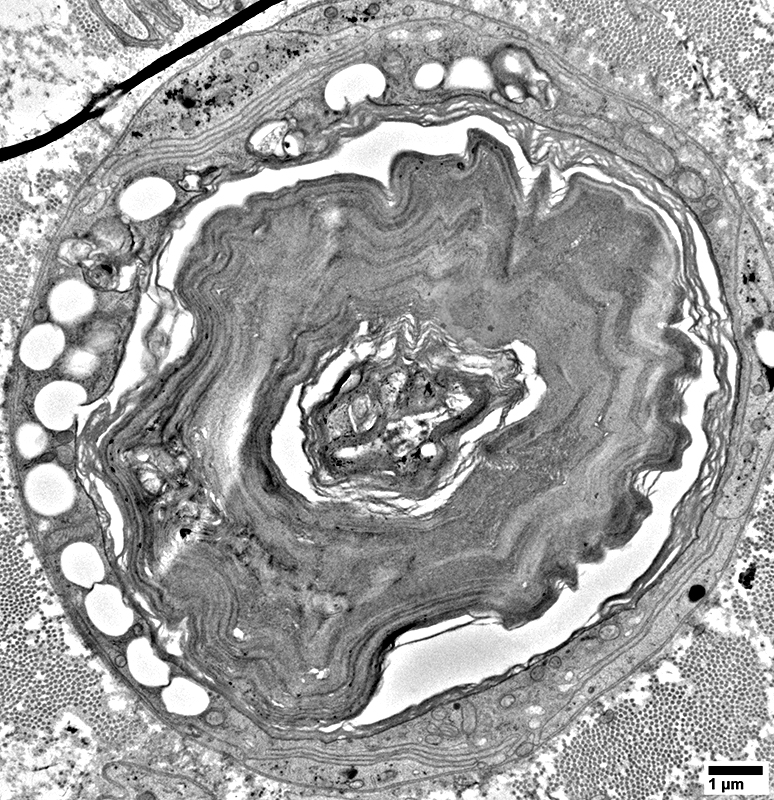

Myelin Damage: Lipid Droplets & Myelin debris in Schwann cells

From: R Schmidt

Myelin Damage: Lipid Droplets & some Myelin debris in Schwann cells